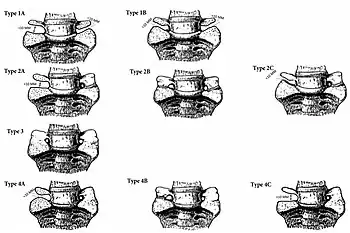

Bertolotti's Syndrome is classified via the Jenkins Classification.[5] The Jenkins classification is separated into 4 categories: Type 1, 2, 3, and 4 with subclassifications of: L (left) or R (right) prominence, A (unilateral), B (bilateral), or C (Type 2 with Type 1 and contralateral 2 anatomy or Type 4 with a gap > 10 mm and contralateral Type 3 anatomy), + L (left) or R (right) iliac contact.

Type 1: A dysplastic transverse process that shows a gap of less than 10mm, but greater than 2mm across the lumbosacral junction.

Type 2: Pseudo-articulation between adjacent transverse processes with a gap of less than 2 mm.

Type 3: Complete fusion lateral to the facet at the ala, without spontaneous fusion of the disk or facet joints, of the lumbosacral junction.

Type 4: Presence of unilaterally fused side with varying pseudoarticulation on the contralateral side (Type 4A, 4B, or 4C).